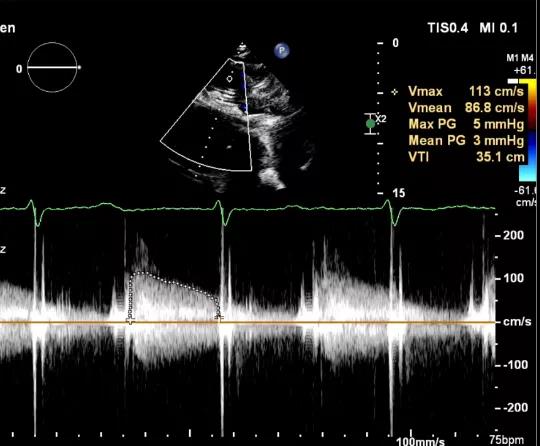

食道超声评估

三尖瓣术前平均压差9mmHg

三尖瓣瓣中瓣术后平均压差3mmHg

术后TV生物瓣活动良好